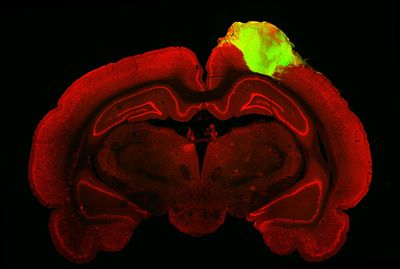

The organoids were grown in the lab for around 80 days before being grafted into their new hosts. The rats used in this experiment were adults, and had sustained injuries to the visual cortex. After three months, the team used a nifty fluorescent-tagged virus, injected into the eye, to track the new connections that the organoids had made with the surrounding tissue.

“By injecting one of these viral tracers into the eye of the animal, we were able to trace the neuronal connections downstream from the retina,” said Chen. “The tracer got all the way to the organoid.”

The big test was to see if the organoid’s neurons could respond to visual stimuli – if so, it would mean that organoids would have the potential to take on the functions of injured brain tissue, and thereby help to repair it. Electrodes were used to probe individual neurons within the organoid, measuring their activity while the animals were exposed to flashing lights and alternating black and white bars.

“We saw that a good number of neurons within the organoid responded to specific orientations of light, which gives us evidence that these organoid neurons were able to not just integrate with the visual system, but they were able to adopt very specific functions of the visual cortex,” Chen explained.